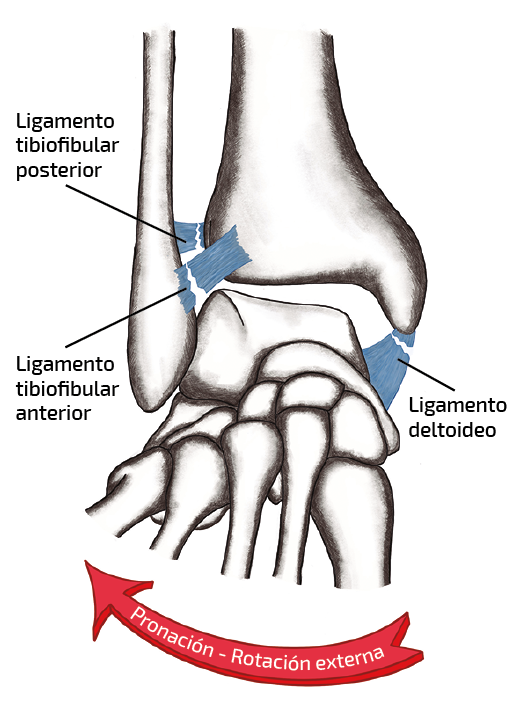

Figura 1. Esquema del mecanismo lesional de la sindesmosis.

Los mecanismos de lesión más frecuentes de la sindesmosis tibioperonea, tanto de forma independiente como especialmente en combinación, son la rotación externa y la dorsiflexión(1)(Figura 1). Según Doughtie(15), más del 70% de las lesiones de la sindesmosis implican un movimiento de rotación externa. Durante la producción de estas lesiones, el pie está fijo en el suelo; la rotación interna de la pierna y el cuerpo con respecto a este da como resultado una rotación externa relativa del astrágalo dentro de la mortaja y del peroné con respecto a la tibia. A medida que el astrágalo se desplaza en rotación externa dentro de la mortaja, esta se ensancha(16). La eversión forzada del astrágalo también la ensancha. La dorsiflexión forzada, además, introduce en la mortaja la cara anterior más ancha de la cúpula astragalina en el espacio articular, abriéndola. En todos los casos, el peroné distal se aleja lateralmente de su articulación con la tibia distal(14), dando lugar, según estudios biomecánicos(16), a un fallo secuencial con un patrón predecible: el LTFAI (el más débil) y el ligamento deltoideo superficial son los primeros en sufrir lesiones. Según progrese la fuerza, se producirá la ruptura del ligamento interóseo (LIO) y de la membrana interósea (MIO). El LTFPI y el fascículo profundo del ligamento deltoideo son los últimos en romperse por completo, lo que lleva a una mayor inestabilidad y/o luxación de la articulación tibiotalar. La severidad de la fuerza aplicada y su duración determina la extensión proximal de la lesión (MIO o peroné proximal). La diástasis completa tibioperonea inferior puede conllevar la luxación superior del astrágalo(17)(Figura 2).